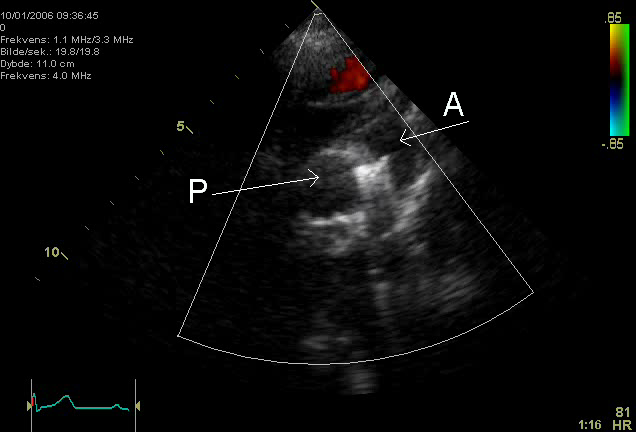

Patent Ductus Arteriosus (PDA)

A patent ductus arteriosus (PDA) results from failure of the ductus arteriosus close.

Patent ductus arteriosus (PDA) is linked to congenital rubella.

Patent ductus arteriosus (PDA) results in a left-to-right shunt between the pulmonary artery and the aorta.

The ductus arteriosus generally diverts blood away from the lungs and toward the aorta during development.

Patent ductus arteriosus (PDA) is typically asymptomatic at birth with a holosystolic ‘machine-like’ murmur.

Patent ductus arteriosus (PDA) may result in lower extremity cyanosis and Eisenmenger syndrome.

Treatment of patent ductus arteriosus (PDA) involves indomethacin, which decreases prostaglandin E1 (PGE1), resulting in PDA closure.

Note that PGE1 maintains patency of the ductus arteriosus.